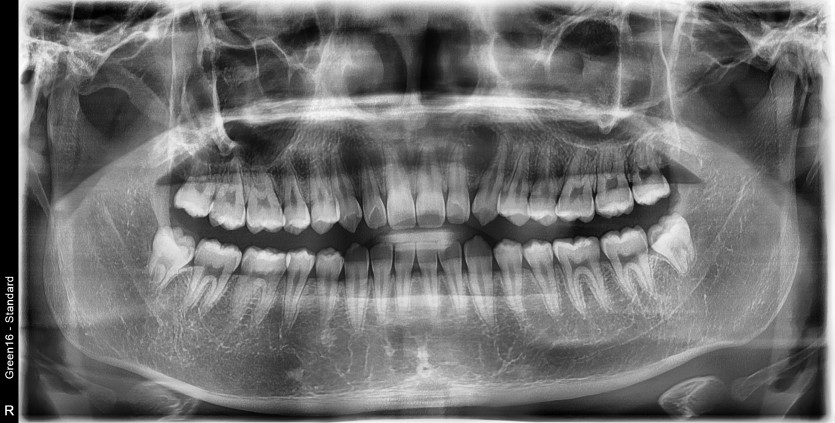

#18,28,38,48 사랑니 발치

구강 외과 전문의가 당일 발치했습니다.